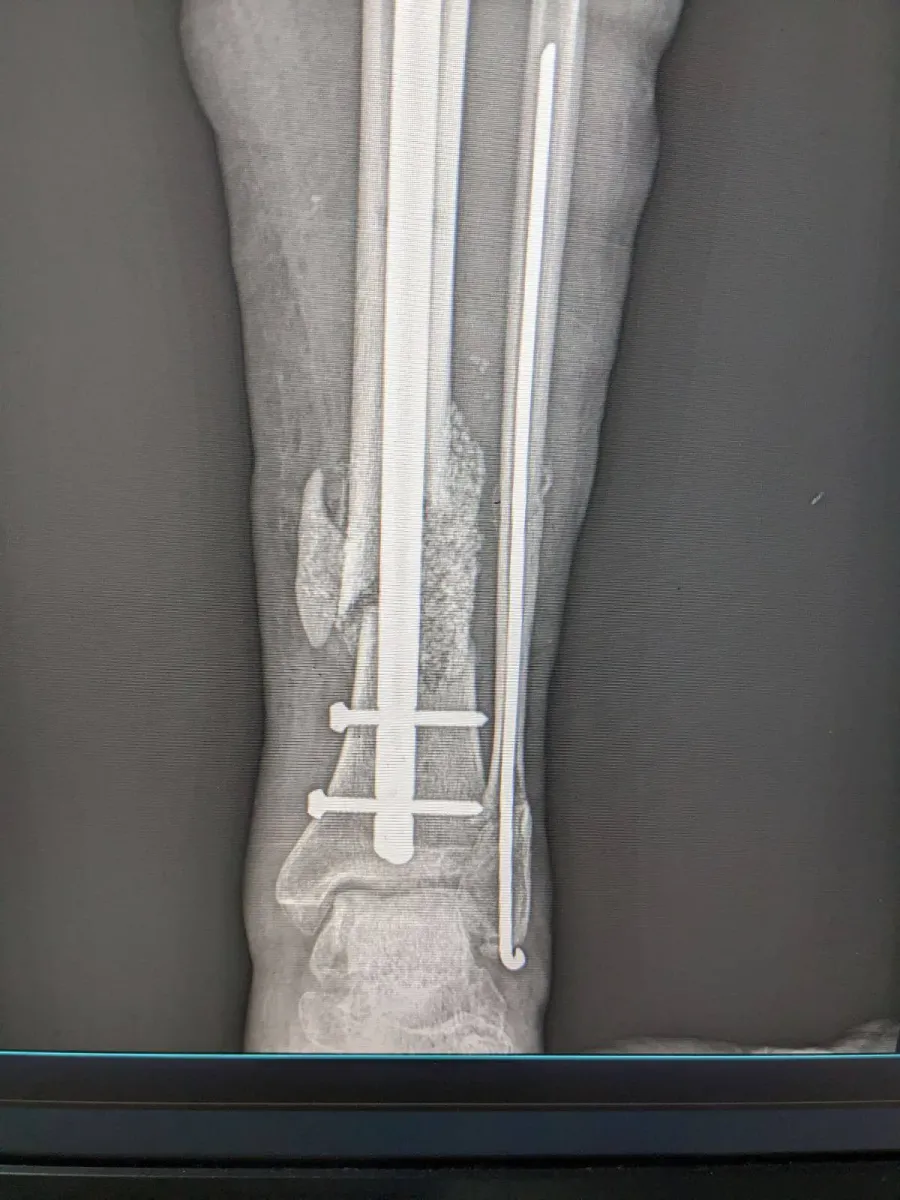

У закладі проведено реконструктивне оперативне втручання військовослужбовцю з післятравматичним дефектом кісткової тканини, повідомляє КНП "Богородчанська центральна лікарня" Богородчанської селищної ради.

Під час операції лікарями було виконано відновлення цілісності кістки із застосуванням аутокісткової пластики (власна кістка пацієнта) у поєднанні з біоактивним біосклом, що дозволяє:

- стимулювати регенерацію кісткової тканини;

- покращити остеоінтеграцію;

- зменшити ризик ускладнень;

- сприяти швидшому функціональному відновленню.

Використане біоскло було придбане за кошти лікарні, що дало можливість забезпечити пацієнта сучасними матеріалами без додаткового фінансового навантаження.

Втручання проведено командою травматологів-ортопедів із дотриманням сучасних принципів реконструктивної хірургії.